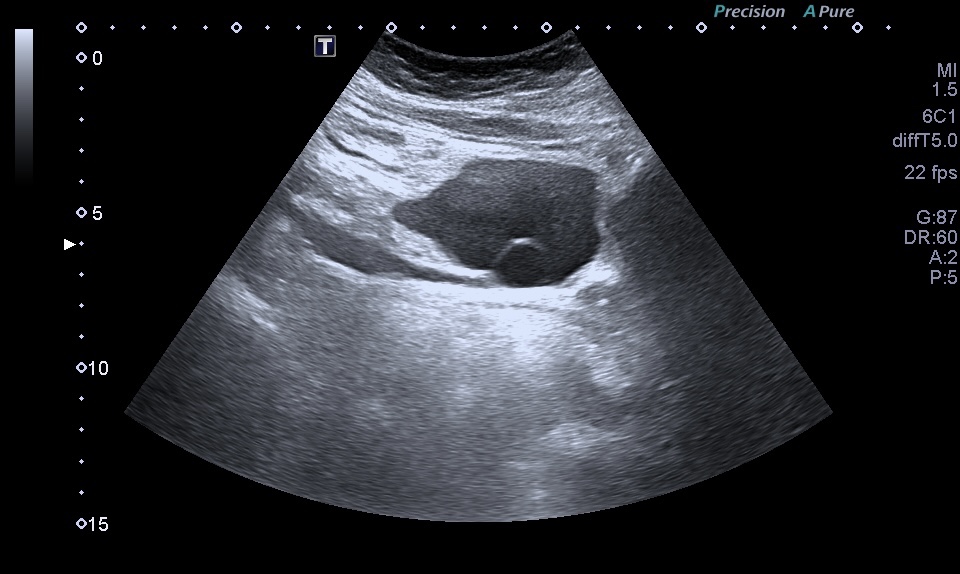

Al realizar una ecografía reno vesical, los hallazgos ecográficos típicos del urotelioma incluyen la visualización de una masa sólida en la vejiga.

Esta masa puede presentar una apariencia heterogénea, con áreas hipoecoicas (menos ecogénicas) y áreas hiperecoicas (más ecogénicas) en relación con el tejido circundante. Además, puede observarse un crecimiento intraluminal, lo que significa que la masa se proyecta hacia el interior de la vejiga.

1. Ubicación: El urotelioma generalmente se encuentra en la mucosa o submucosa de la vejiga. Puede presentarse como una lesión focal o múltiple.

2. Apariencia ecográfica: El urotelioma se muestra como una masa sólida con una ecogenicidad variable en comparación con el tejido circundante. Puede presentar áreas hipoecoicas (menos ecogénicas) y áreas hiperecoicas (más ecogénicas).

1. Contornos: Los contornos de la masa pueden ser irregulares y asimétricos. Pueden observarse proyecciones intraluminales, lo que indica que la masa se extiende hacia el interior de la vejiga.

1. Estructura interna: La estructura interna del urotelioma puede ser heterogénea debido a la presencia de áreas de necrosis o hemorragia. Estas áreas pueden ser identificadas por su apariencia hipoecoica o hiperecoica respectivamente.También calcificiones…como es el caso que nos ocupa hoy.

Masa tipo